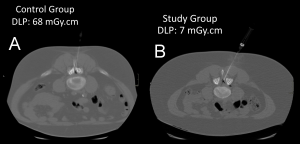

The Dose Length Product (DLP) in the study group was significantly lower than in the control group (Table 2; Figure 1).

The study group had a mean total DLP of 134.71 mGy.cm, compared to 313.13 mGy.cm in the control group. This equates to a dosage reduction of 56.97%.

The mean DLP for diagnostic acquisitions was 89.46 mGy.cm in the study group against 128.43 mGy.cm in the control group. This equates to a dosage reduction of 30.34%.

The mean DLP for minimal dose acquisitions was 9.77 mGy.cm in the study group against 44.71 mGy.cm in the control group. This equates to a dosage reduction of 78.4%.

The needle tip visibility did not differ significantly between the two groups (p = 1.0, Chi-square test) (Figures 2, 3, 4, and 5). The needle tip was visible in nearly every patient in this study (170 out of 171).